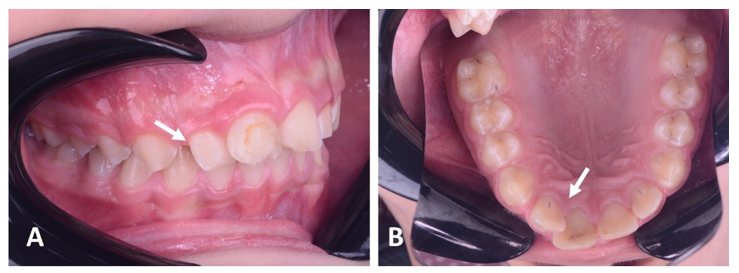

The panoramic radiograph showed a periapical radiolucency between the central and lateral upper right incisors (Teeth # 12 and 11), and a confirmatory periapical radiograph revealed a large, well-defined radiolucency in the periapical region between the two teeth with severely diverged roots (Figure 2).

Figure 2 A panoramic radiograph shows tilted roots of the right lateral incisor due to pressure of the periapical lesion (circle). A preapical radiograph shows a large periapical lesion (14x26mm) with diverged roots of related teeth(# 12 and 11).